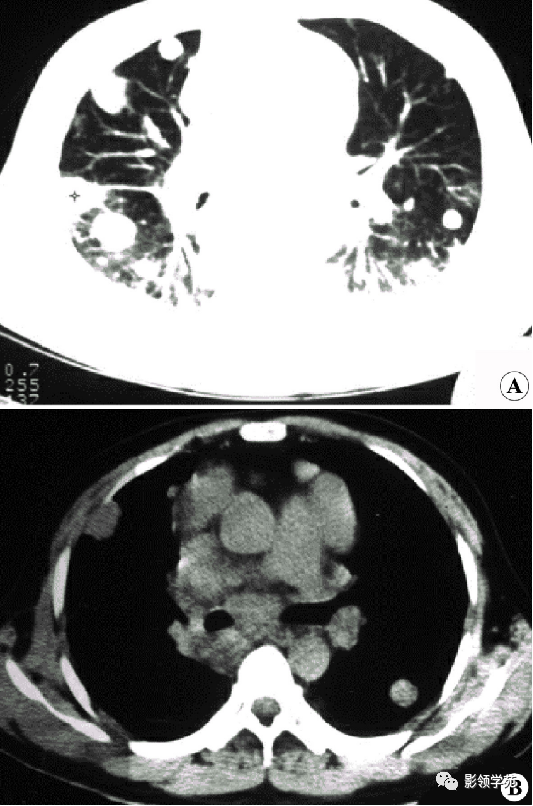

肺转移瘤。

肺窗像(A)示双肺野可见大小不等的圆形高密度结节影,纵隔增宽;纵隔窗像(B)示肺内肿块呈实性,纵隔满布大小不等的肿大淋巴结

CT诊断:甲状腺癌双肺多发转移